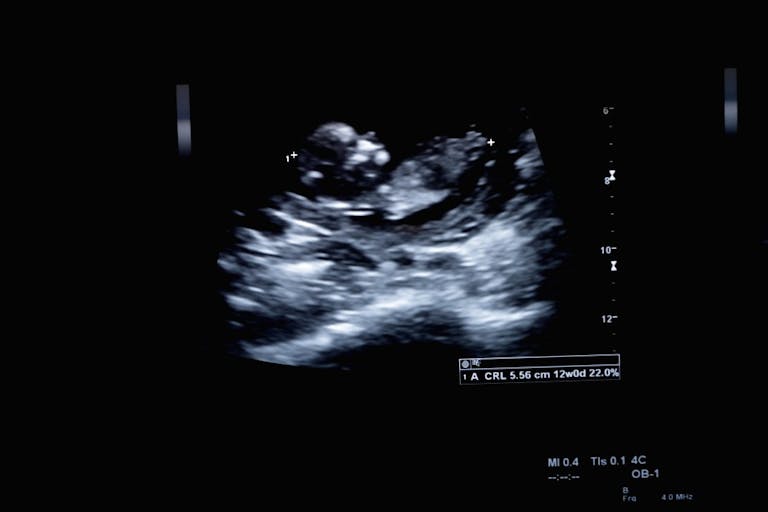

HB 1459 proposed that an ultrasound be required before a woman has an abortion. This type of bill exists in others states, and while controversial to abortion advocates, is an important part of informed consent, as abortion providers like Planned Parenthood have been caught giving women inaccurate information on fetal development. According to Guttmacher Institute, the withdrawn Tennessee bill is one that exists in several states…

10 states mandate that an abortion provider perform an ultrasound on each woman seeking an abortion, and require the provider to offer the woman the opportunity to view the image.

3 states mandate that an abortion provider perform an ultrasound on each woman seeking an abortion and requires the provider to show and describe the image.